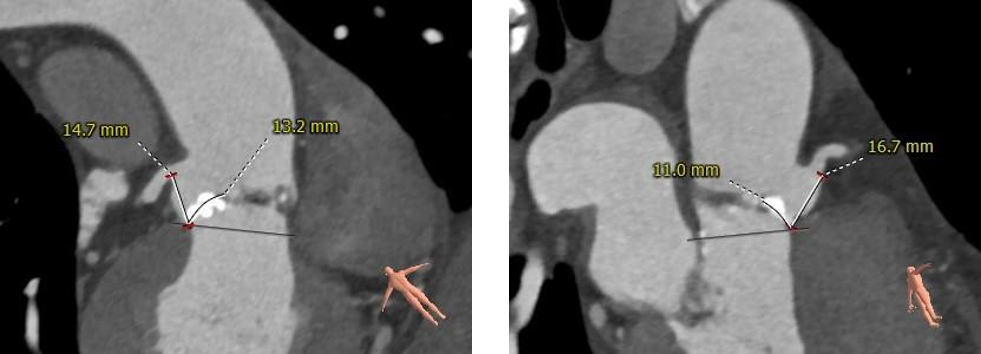

术前CT评估:

主动脉根部评估:

植入后评估:

植入后血流动力学改善明显